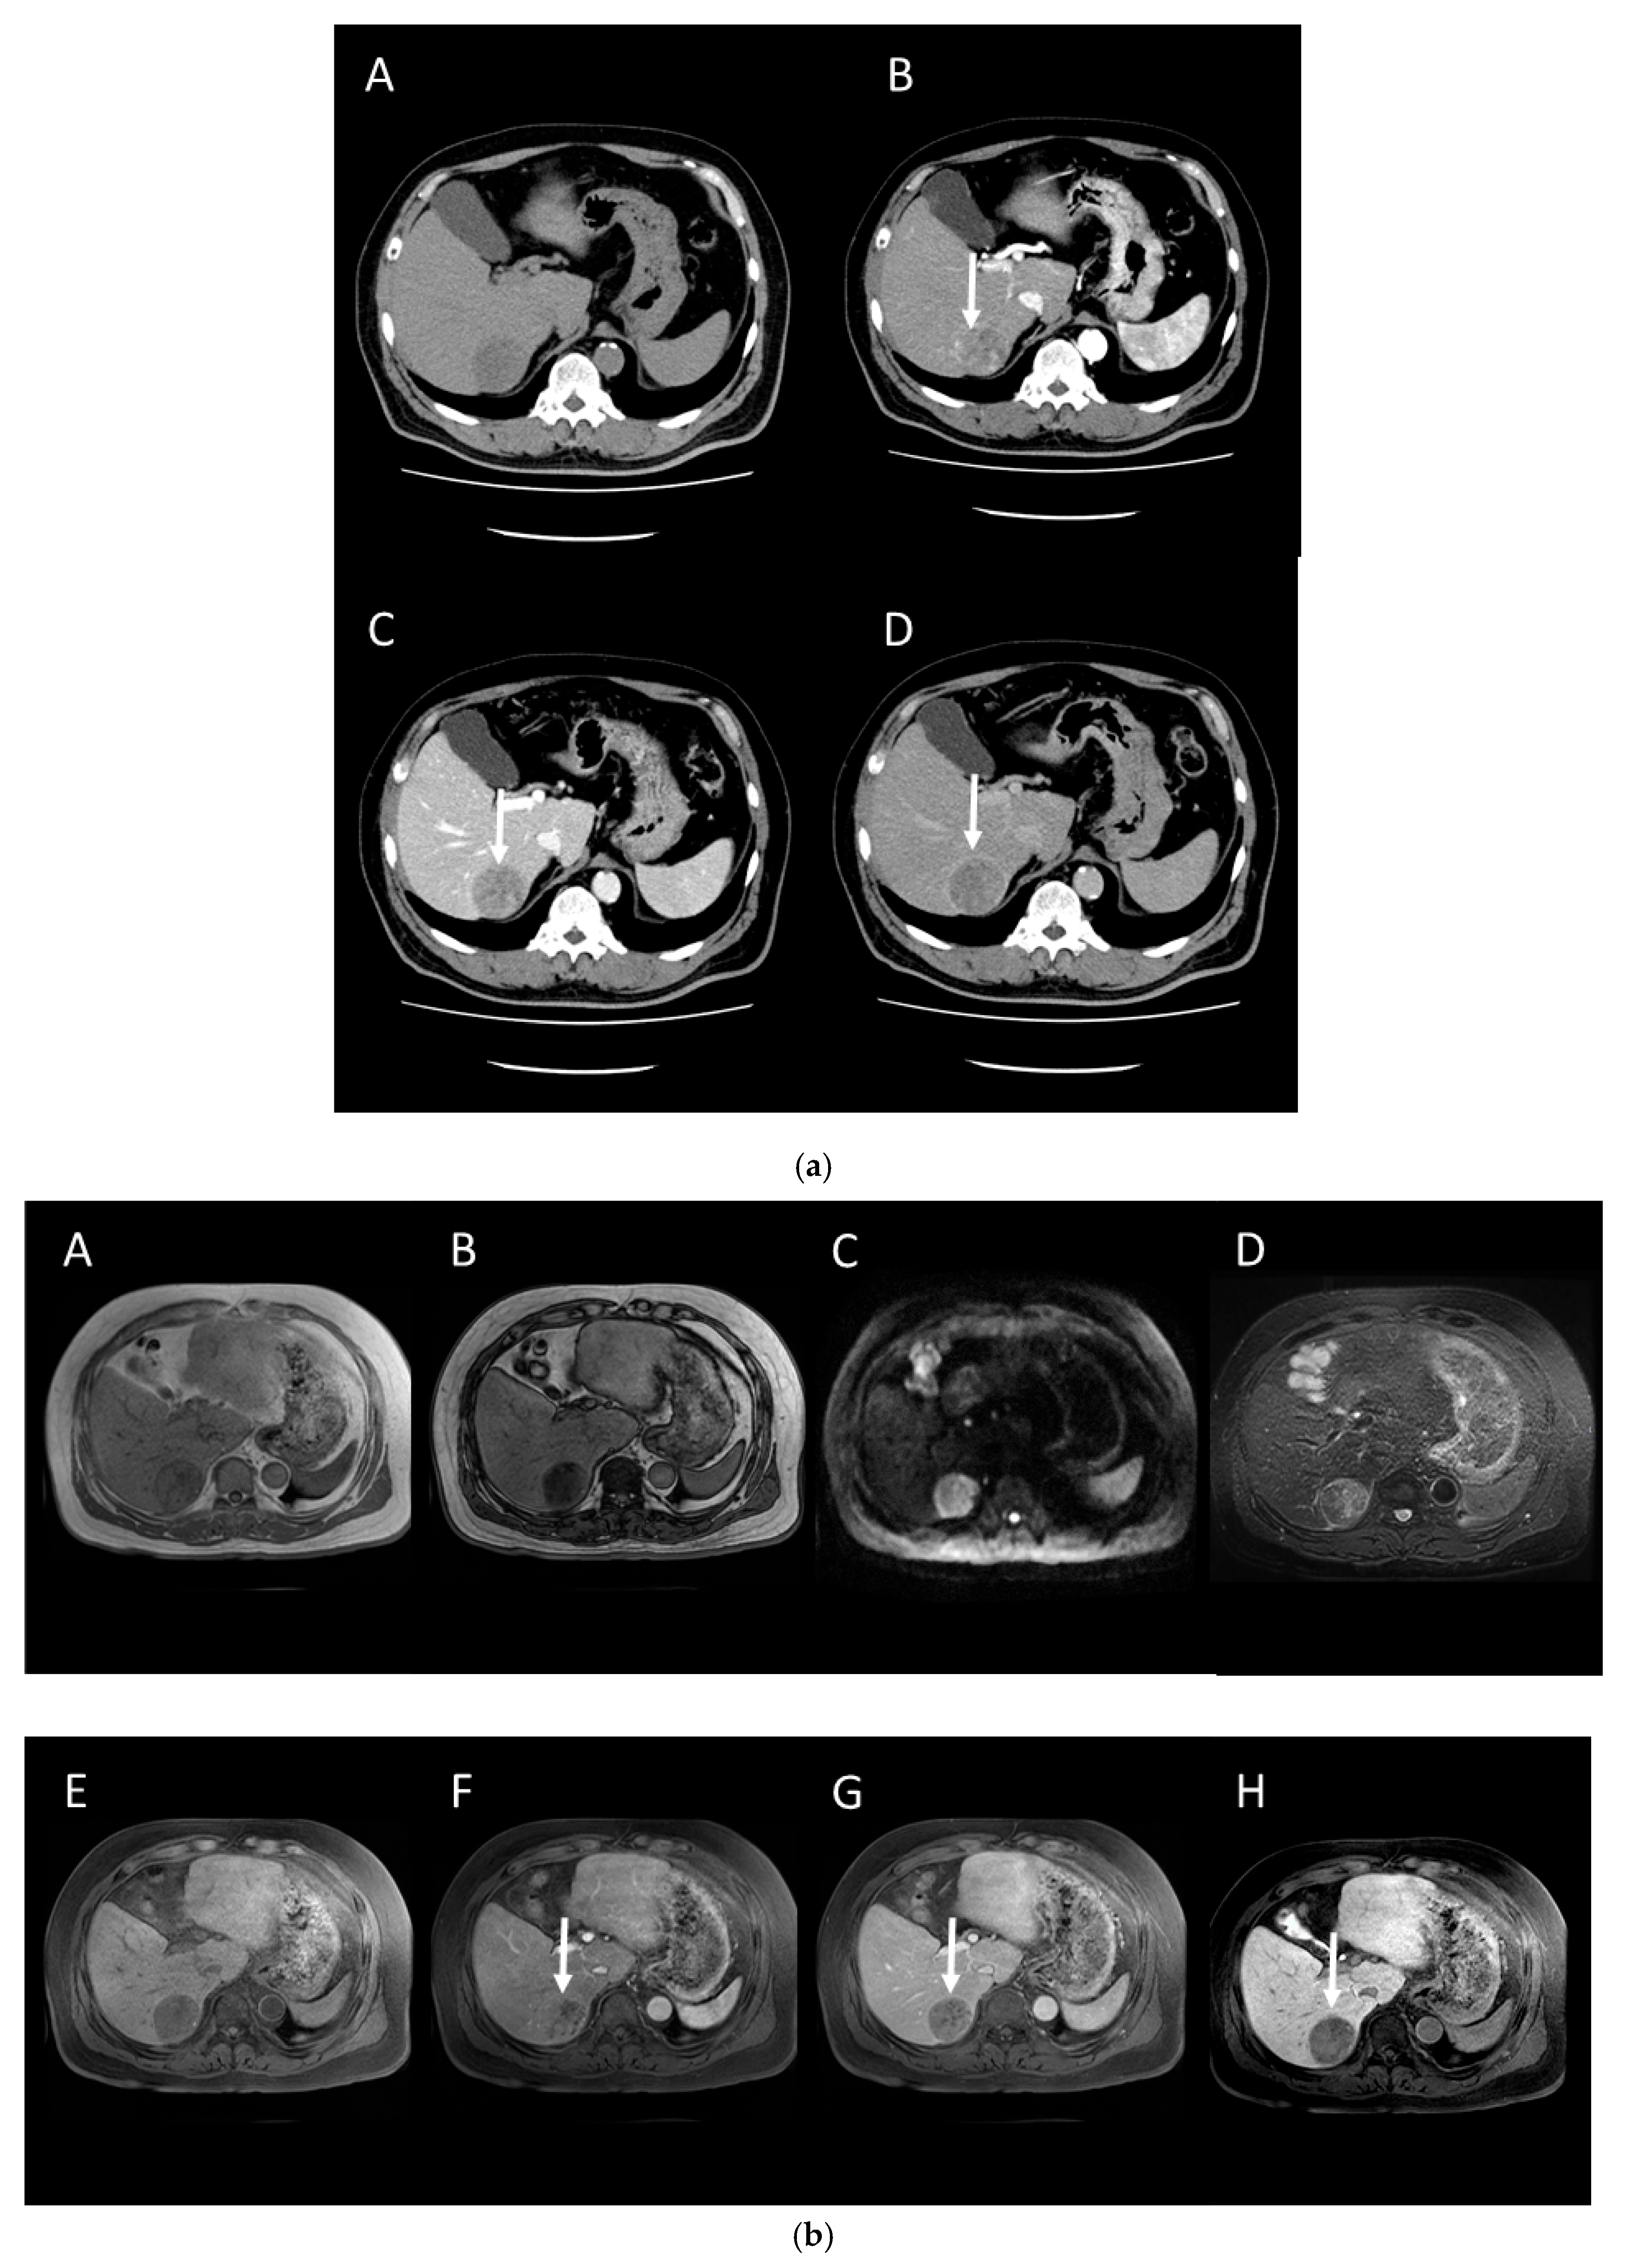

4.4. Moderately Differentiated Hepatocellular Carcinoma (Moderately HCC)

4.5. Poorly Differentiated Hepatocellular Carcinoma (Poorly HCC)